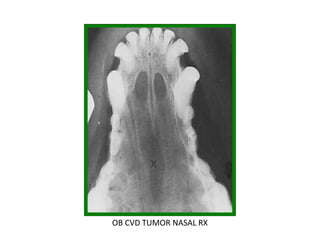

OB CVD 18 Neoplasia cavidad nasal

OB CVD TUMOR NASAL RX